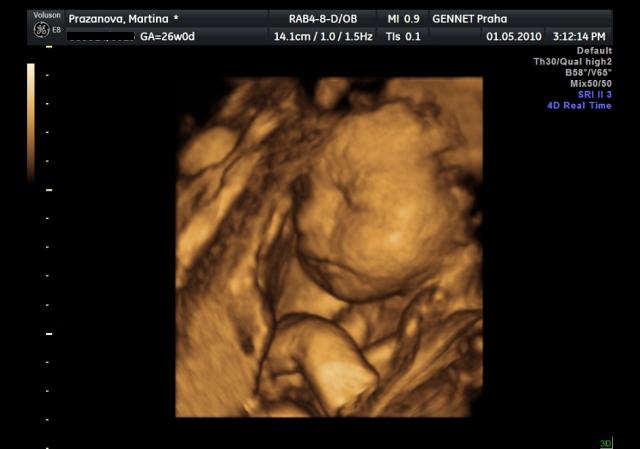

Už se nemůžeme dočkat 1.5....jdeme na 4D UTZ, tak doufám, že se nám ten náš klučík ukáže v plné své kráse 🙂))